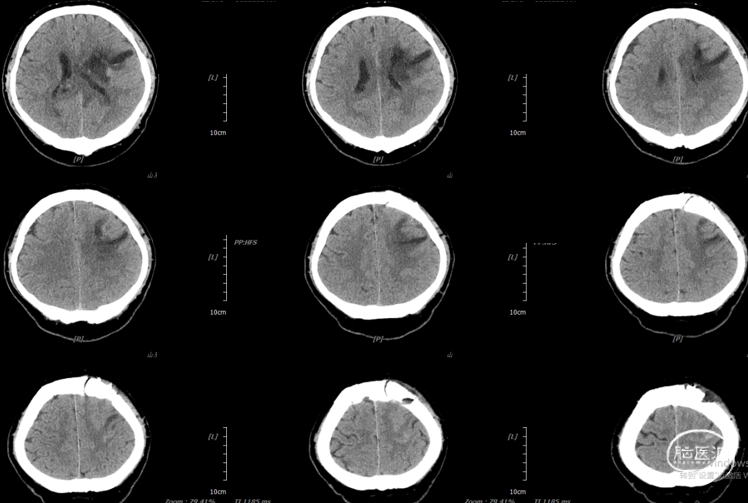

2026.3.14术后即刻:

气管插管全麻成功后,患者取平卧位,上半身抬高20°,头微屈,头架固定,延导航标记左侧冠状缝前3cm,中线旁开3cm弧形手术刀口,长度约5cm,常规消毒铺巾,依次切开皮肤、皮下及骨膜各层,钻骨孔一个,铣成大小约3.0cm*3.0cm骨窗,电灼硬膜,“十”字状切开硬膜,置神经内镜,探查左侧基底节发现大量暗红色脑内血肿,内镜下彻底清除基底节区血凝块约80ml后脑组织压力较前明显降低,见血肿前方、侧方深部各有活动性出血,血肿底部可疑小型异常血管团,予以电凝彻底止血,并切除部分送病理,止血材料覆盖血肿腔,术区冲洗未见活动性出血,向内侧沿着血肿破入脑室痕迹探查,暴露脑室体部,清除脑室内大量血凝块,并反复使用生理盐水冲洗,再次探查见基底节区血肿腔止血充分,无活动性出血,温盐水冲洗术野,使用流体明胶压迫并接触止血,血肿腔留置12号侧脑室引流管1根,硬膜下留置codman颅内压传感器一根(偏移值520),以连接板将骨瓣还纳,清点棉片器械无误,依次缝合皮下及皮肤各层。将引流管皮下潜行后固定引流管,手术顺利,术中出血约20ml,未输血,术后呼吸改善,复查CT示基底节及脑室内血肿清除满意,带气管插管安返我科监护室。